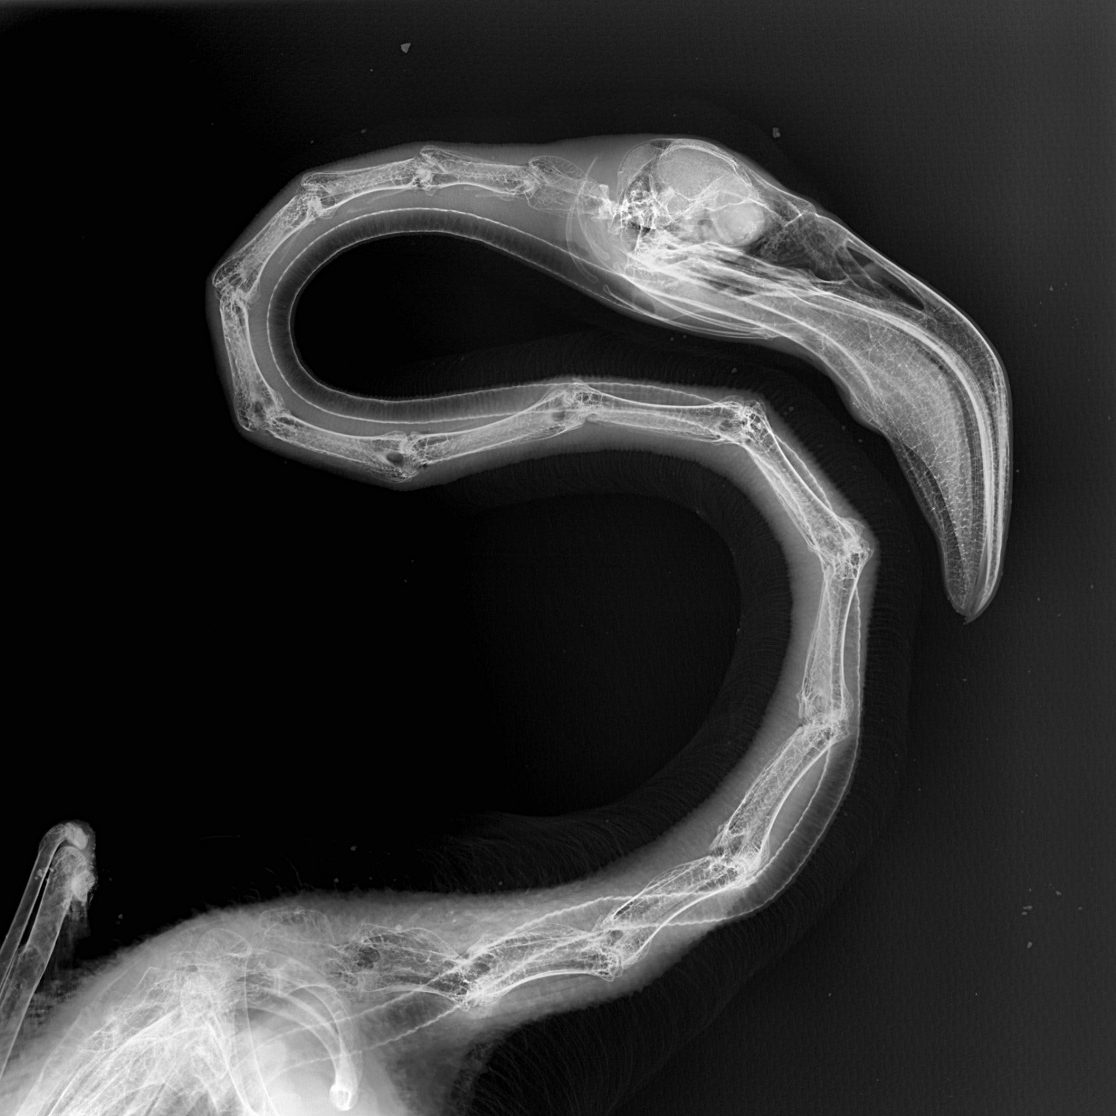

Este procedimiento diagnóstico permite a nuestros expertos brindar una excelente atención médica. Al exponerlos a los rayos X, el equipo puede tomar fotografías de las partes óseas internas de los animales, comprobando la existencia de lesiones o enfermedades que a simple vista no podrían ser identificadas.

Pero, ¿cómo se toma una radiografía de un tigre de Sumatra, de un cálao Gorginegro, un flamenco o un encantador armadillo de tres bandas?

Sin embargo, otros animales no necesitan de esta inmovilización química para hacerles radiografías, es el caso de los armadillos. Con ellos basta con un manejo físico y una buena parte de colaboración voluntaria por su parte. “En ocasiones nos valemos de un proceso de entrenamiento previo que llamamos ‘entrenamiento médico’, en el que el animal recibe una recompensa si nos permite realizar estos estudios de manera voluntaria, sin sujeción física y sin anestesia”.

Por supuesto, para la realización de todo procedimiento diagnóstico o manejo veterinario, el equipo de Bioparc Fuengirola se asegura de que los animales no sufran ningún tipo de estrés en el examen médico, rutinario o de urgencia. Y no solo los animales, también los veterinarios y los cuidadores están en todo momento protegidos, por ejemplo, las radiografías se toman con equipos de protección radiológica, que minimizan los efectos de los rayos x en el operador/es del equipo y en el propio paciente.